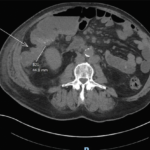

Malignant Tumors of the Small Intestine: A Case Series and Review of the Literature

Small bowel neoplasms are uncommon gastrointestinal malignancies, but their incidence has risen in recent years. The main subtypes include adenocarcinoma and neuroendocrine tumors, each accounting for approximately 40% of cases, […]